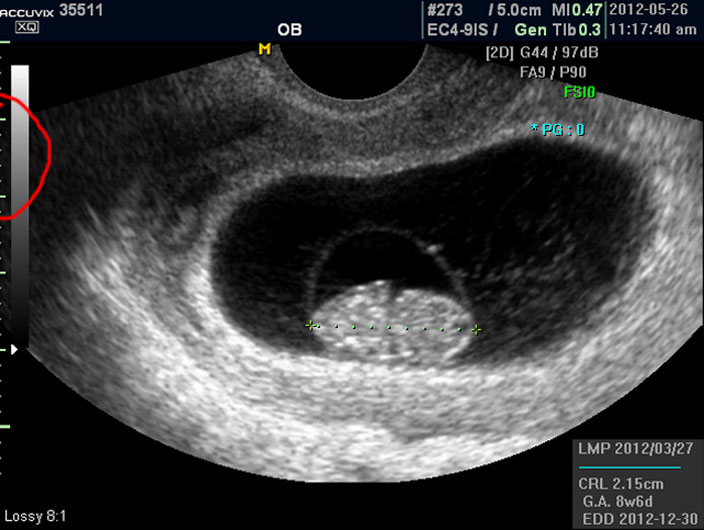

그러나 임신 8주 정도의 초기에는 아직 아기가 쌀알 보다 조금 큰 정도이기 때문에 인간의 형체가 또렷하지는 않습니다.

그저 머리와 몸통 부분만 형성되어 있는 상태이지요.

그리고 초음파 검사에서는 산전 초음파 이외의 다른 경우도 그렇지만 물에 가까운 성분일수록 검게 나오고 뼈처럼 단단해서 초음파 선이 투과하지 못하는 부분은 하얗게 나타납니다.

이는 투과 선은 다르지만 X 레이 검사 사진에서도 마찬가지입니다.

양수 바깥의 조금 회색으로 보이는 얼룩덜룩한 부분이 아기를 품고 있는 자궁이며 근종이나 기타 이상은 없는지 체크하지만 여기서는 산과 부분만 설명하기로 했기 때문에 따로 설명드리지 않습니다.

이런 기준이나 지표들이 표시되는 것은 초음파 장비마다 조금씩 차이가 있고 위치도 다르지만 대개 비슷한 모양이라 한가지를 알면 다른 기종에서도 감상에 그리 어렵지는 않습니다.

참고로 저희는 국산 장비인 메디슨의 고급 기종인 아큐빅스라는 장비를 사용하고 있습니다.